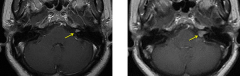

听神经瘤好治吗?术后避免面瘫

听神经瘤,也称为前庭神经鞘瘤,是八脑神经的非恶性肿瘤。...